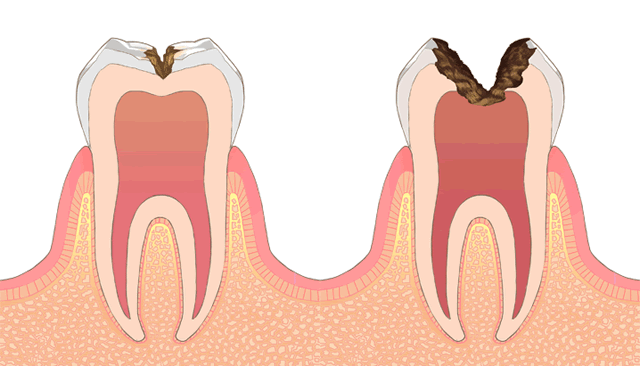

C4

既に根管治療(神経の治療)を受けたことのある歯や、むし歯を放置しすぎて自然に神経が死んでしまった歯では痛みが出ることがなくむし歯が進行します。ご自身の歯の根がどれだけ残せるか、両隣に歯があるのか、お口全体の咬み合わせの状態で治療方針が変わってきます。治療回数としては、即日や、経過観察や型取りすることも含め2回以上、根管治療や補綴治療が必要であれば5回から8回程要します。

根管治療

根管治療とは、歯の中の治療で、神経(血流)の存在する管の部分を拡大して清掃する治療です。根管治療には2種類あり、神経がある歯にする抜髄(つまり、その歯にとって初めての神経の治療ということです)と、既に神経を失っている歯にする感染根管治療(既に治療を受けたことがあるか、自然に失活してしまったか)があります。概念が異なるだけで治療内容は同じです。

主には、むし歯が原因で根管治療が必要になります。むし歯が深く、神経の管の部分に波及している場合には、神経(血流)は根の先まで広がっていますので広く感染してしまっています。その歯を土台として使うには複雑な感染部分を綺麗にしないといけないので、歯の種類や病状によって異なりますが3回から6回程かけて根管治療をしていきます。

根管治療にも、成功率があり、むし歯になったからといって生涯何度でも治療がやり直せて被せられるというわけではありません。むし歯になったり、治療をするごとに少しずつ歯は小さくなっていき土台としての強度は弱くなってしまいます。”痛くなってから治療すればいいかな” ”今は忙しいから、、”というお考えではなくぜひ些細な症状のうちにお越しいただくことをお薦めいたします。